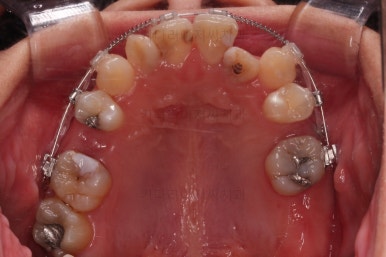

초진 시 입안의 모습입니다.

이미 썩어서 부러진 치아도 몇 개 보이고요.

많이 삐뚤어진 치아쪽은 양치가 힘들어 이미 많이 썩어 있는 상태에 덧니쪽은 잇몸도 많이 내려간 상태였습니다.

말그대로 교정치료 뿐만 아니라 전반적인 치료가 필요한 상황이었습니다.